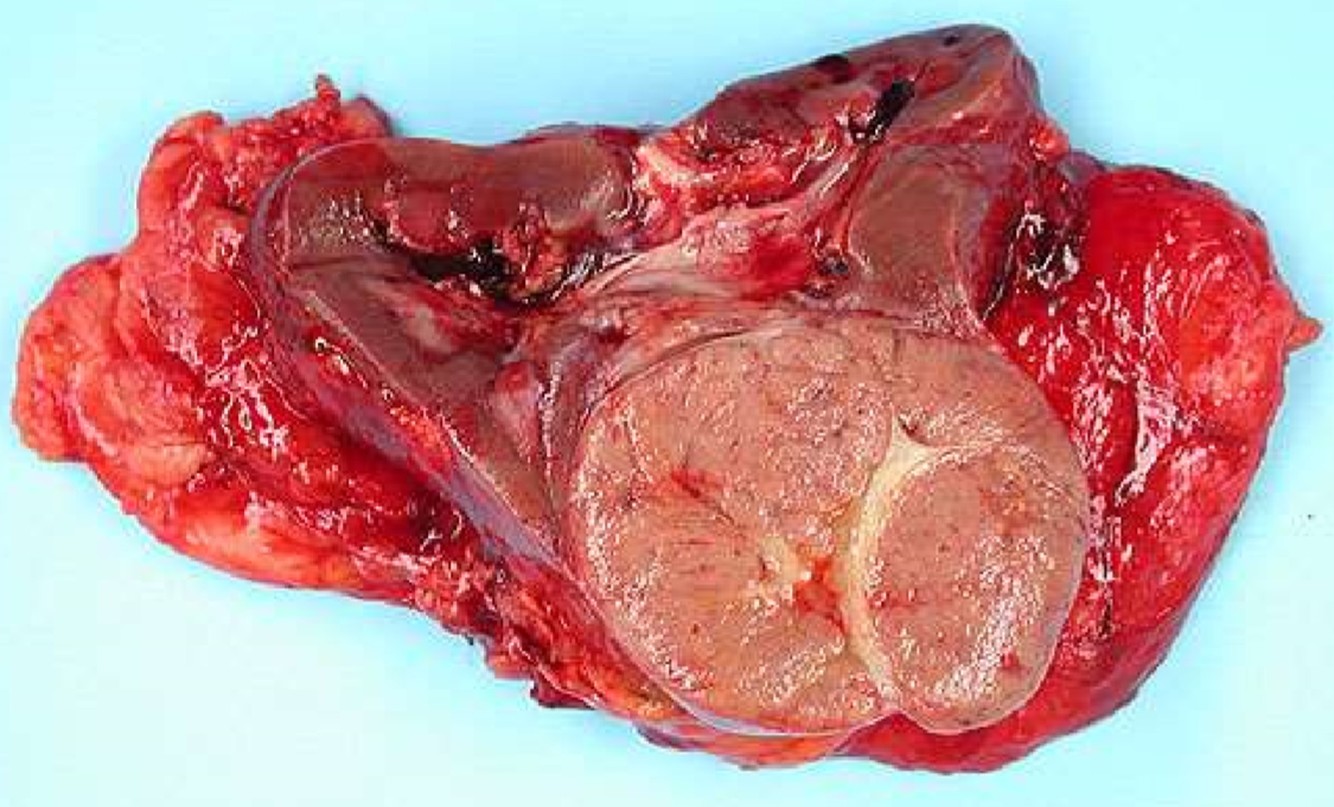

CHROMOPHOBE RCC

- Gross:

- Presents as a cortical neoplasm, classically mahogany brown in color